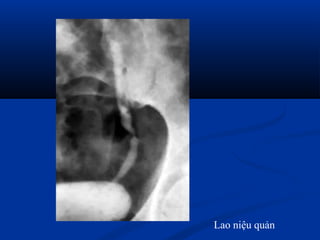

Lao niệu quản